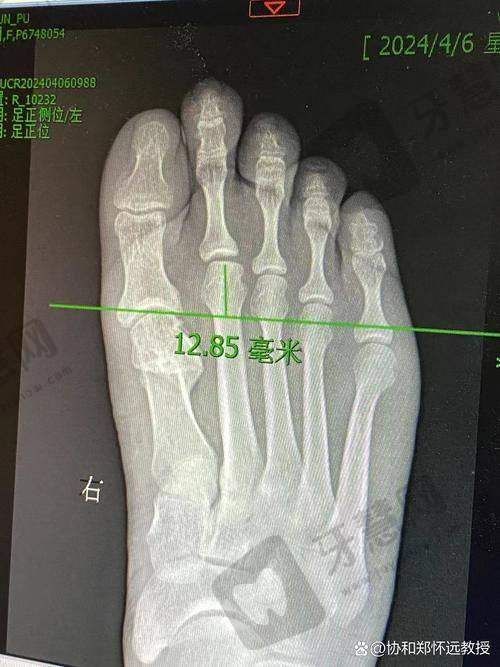

陈女士的求医之路可谓坎坷。七年前,她在当地医院接受了传统的"截骨+钢钉内固定"手术,本以为能够一劳永逸,却没想到这只是痛苦的开始。术后出现的截骨过度、角度矫正不足、内固定移位等问题,让她的右脚状况比术前更加糟糕。

随着时间的推移,畸形不断加重:关节半脱位、足弓塌陷、局部瘢痕增生、骨赘增生等问题相继出现。更让她难以忍受的是持续的疼痛——行走超过15分钟就会剧痛难忍,更别提穿高跟鞋了。"那七年间,我询问了无数医生,得到的答复都是'太复杂,不好修',直到我听说了苏敬达医生。"

外地患者面诊时务必带齐所有既往手术记录和近3个月内拍摄的双足负重位X光片。建议预留一整天时间,因为面诊和检查通常需要较长时间。如果确定手术,还需要与助理沟通排期,苏医生的手术通常需要提前1-3个月预约。